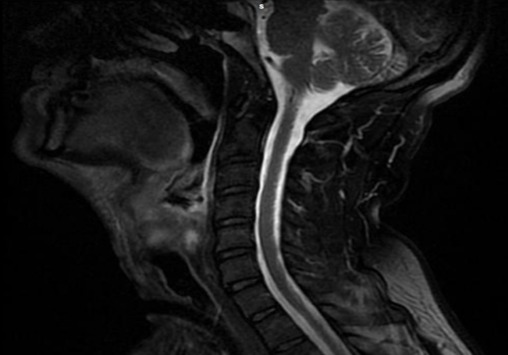

Рентгенологические методики

- МРТ/ КТ мягких тканей шеи с применением внутривенного контрастирования — обеспечивают данные о распространении патологического процесса по отделам гортани, а также дают информацию по регионарному лимфатическому коллектору;

Рентгенологические методы исследования